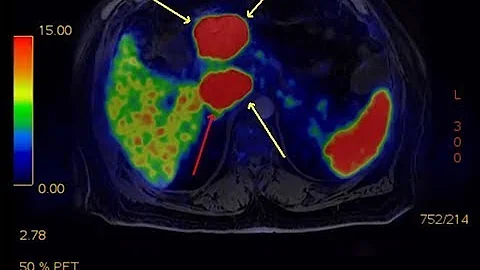

Pancreatic neuroendocrine tumors (PNETs) are a group of cancers that can occur in the hormone-producing cells of the pancreas ...